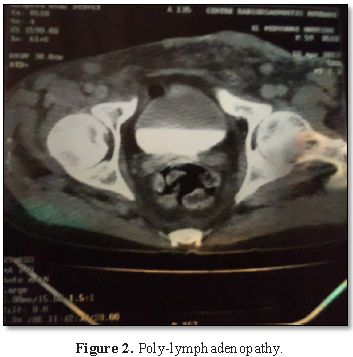

In order to investigate the underlying etiology, the ultrasound showed axilliary necrotic lymph nodes that were biopsied revealing an active tuberculoid granulomatous adenitis without caseous necrosis. The abdominal ultrasound (Figure 1) also showed several necrotic coelio-mesenteric lymphadenopathies, the largest of which measured 2.5 cm of minor axis. Both kidneys were increased in hyper-dedifferentiated size (in favor of acute functional renal failure). And in thoraco-abdominopelvic CT (Figure 2), mediastinal and abdominal polyadenopathies with mild hepatomegaly, splenomegaly and coelio-mesenteric and hilar hepatic adenopathies. Although the search for Koch bacilli in the sputum was negative, however the chest x-ray showed a hilar opacity and the tuberculin intradermoreaction was positive at 20 mm of phlyctenular appearance. Thus, the diagnosis of pulmonary and hematopoietic tuberculosis was carried out.